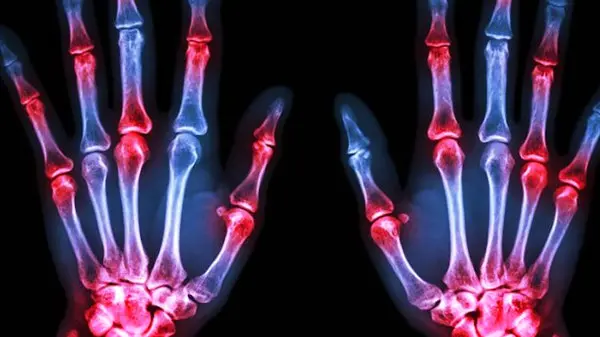

آرتریت روماتوئید (Rheumatoid Arthritis):

یک بیماری خودایمنی است که باعث التهاب مزمن در مفاصل میشود. این بیماری میتواند به تخریب مفاصل و کاهش دامنه حرکت آنها منجر شود.